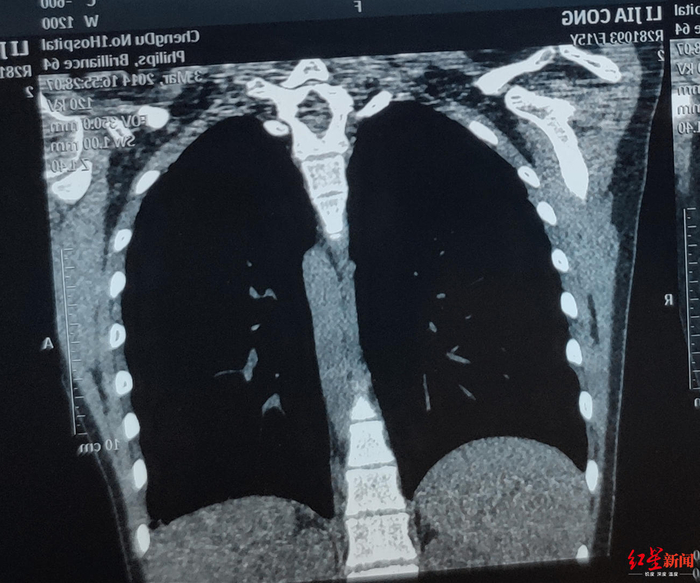

↑术前评估气管狭窄段较长

女孩入院后,治疗团队就着手进行病情评估。检查发现气管上段有3-6cm长度的瘢痕狭窄区域,此区域因瘢痕挛缩过重,用球囊扩张难以达到最佳效果。而且,患者将承受球囊扩张后气道破裂损伤甚至致命风险,因此手术切除是其唯一出路。